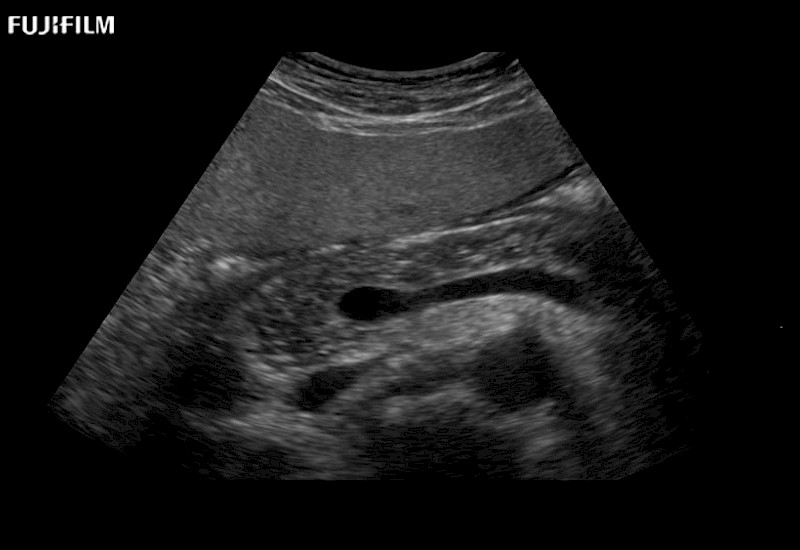

Extraordinary high-resolution digital imaging

- Instant feedback on tumor margin delineation

- Valuable information to guide tumor resections

- Instant feedback on tumor margin delineation

- Instant feedback on tumor margin delineation

- Instant feedback on tumor margin delineation

- Instant feedback on tumor margin delineation

- Instant feedback on tumor margin delineation

- Instant feedback on tumor margin delineation

- Instant feedback on tumor margin delineation

- Instant feedback on tumor margin delineation

- Instant feedback on tumor margin delineation